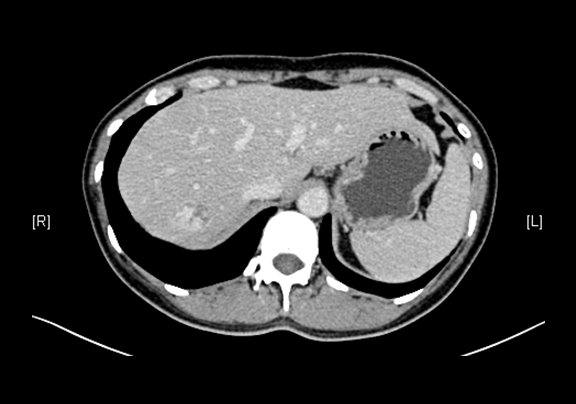

上腹部增强CT示:肝右叶海绵状血管瘤可能性大;肝囊肿;左肾上极肿瘤可能性大;双肾多发囊肿。

术前CT检查:

动脉期